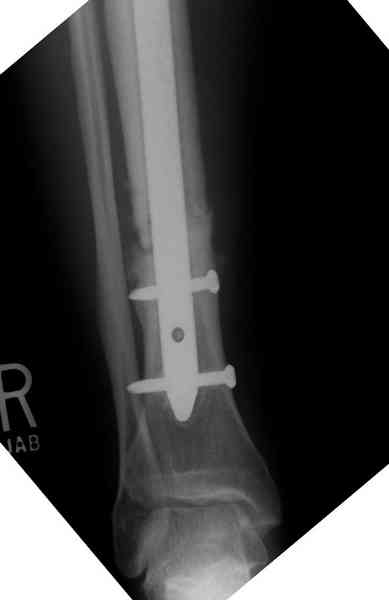

The cages are commercially available but up to 10 cm. So we measured the needed length on x-rays, added 2 cm at both ends for sure that

the resected piece will include all, and resulted with 15 cm which one was ordered and individually made by the same factory. So yes, we made the gap to fit the cage.

The inner diameter of the tube is 13 mm, the nail was 12 mm, so not so much space to put something inside. Yes, this is really shaft endoprosthesis which i hardly ever would offer for a young football player. Though... Maybe we would when we collect some experience with this sort of implants to feel/prognose its strength in different settings.

Нет. Просвет внутри кейджа - 13 мм, штифт - 12 мм. Не так там и много пространства то есть. Но вопрос правильный, интересный, из разряда современных нерешенных проблем.